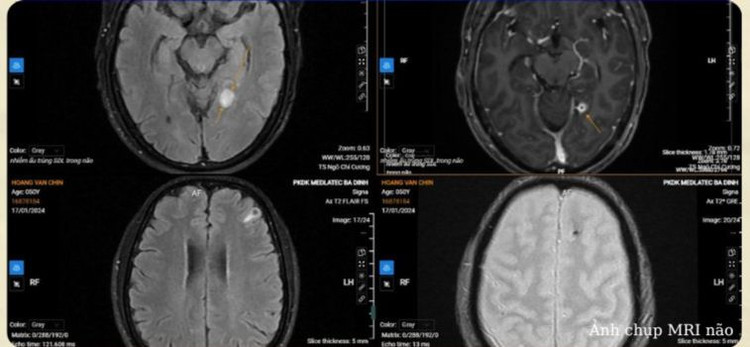

Tại bệnh viện, các bác sĩ chụp X-quang cho bệnh nhân thấy các nốt vôi hóa vùng cổ, vai, ngực, bụng, hướng tới tổn thương do ký sinh trùng. Trên hình ảnh chụp MRI não phát hiện tổn thương vùng chẩm hai bên, nốt vôi đồi thị rải rác hai bán cầu đại não, tiểu não.

Chẩn đoán xác định, tình trạng của bệnh nhân là tổn thương não do ký sinh trùng. Bệnh nhân C. được kê đơn điều trị và theo dõi chặt chẽ tình hình sức khỏe.